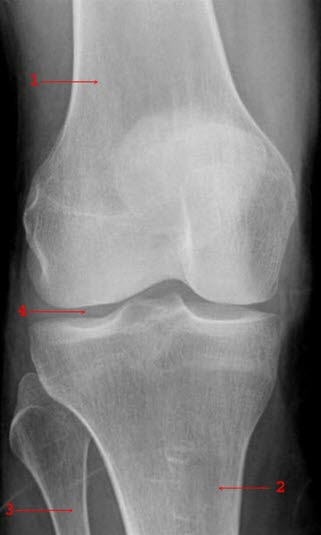

Se røntgenbilde av kneleddet forfra og fra siden.